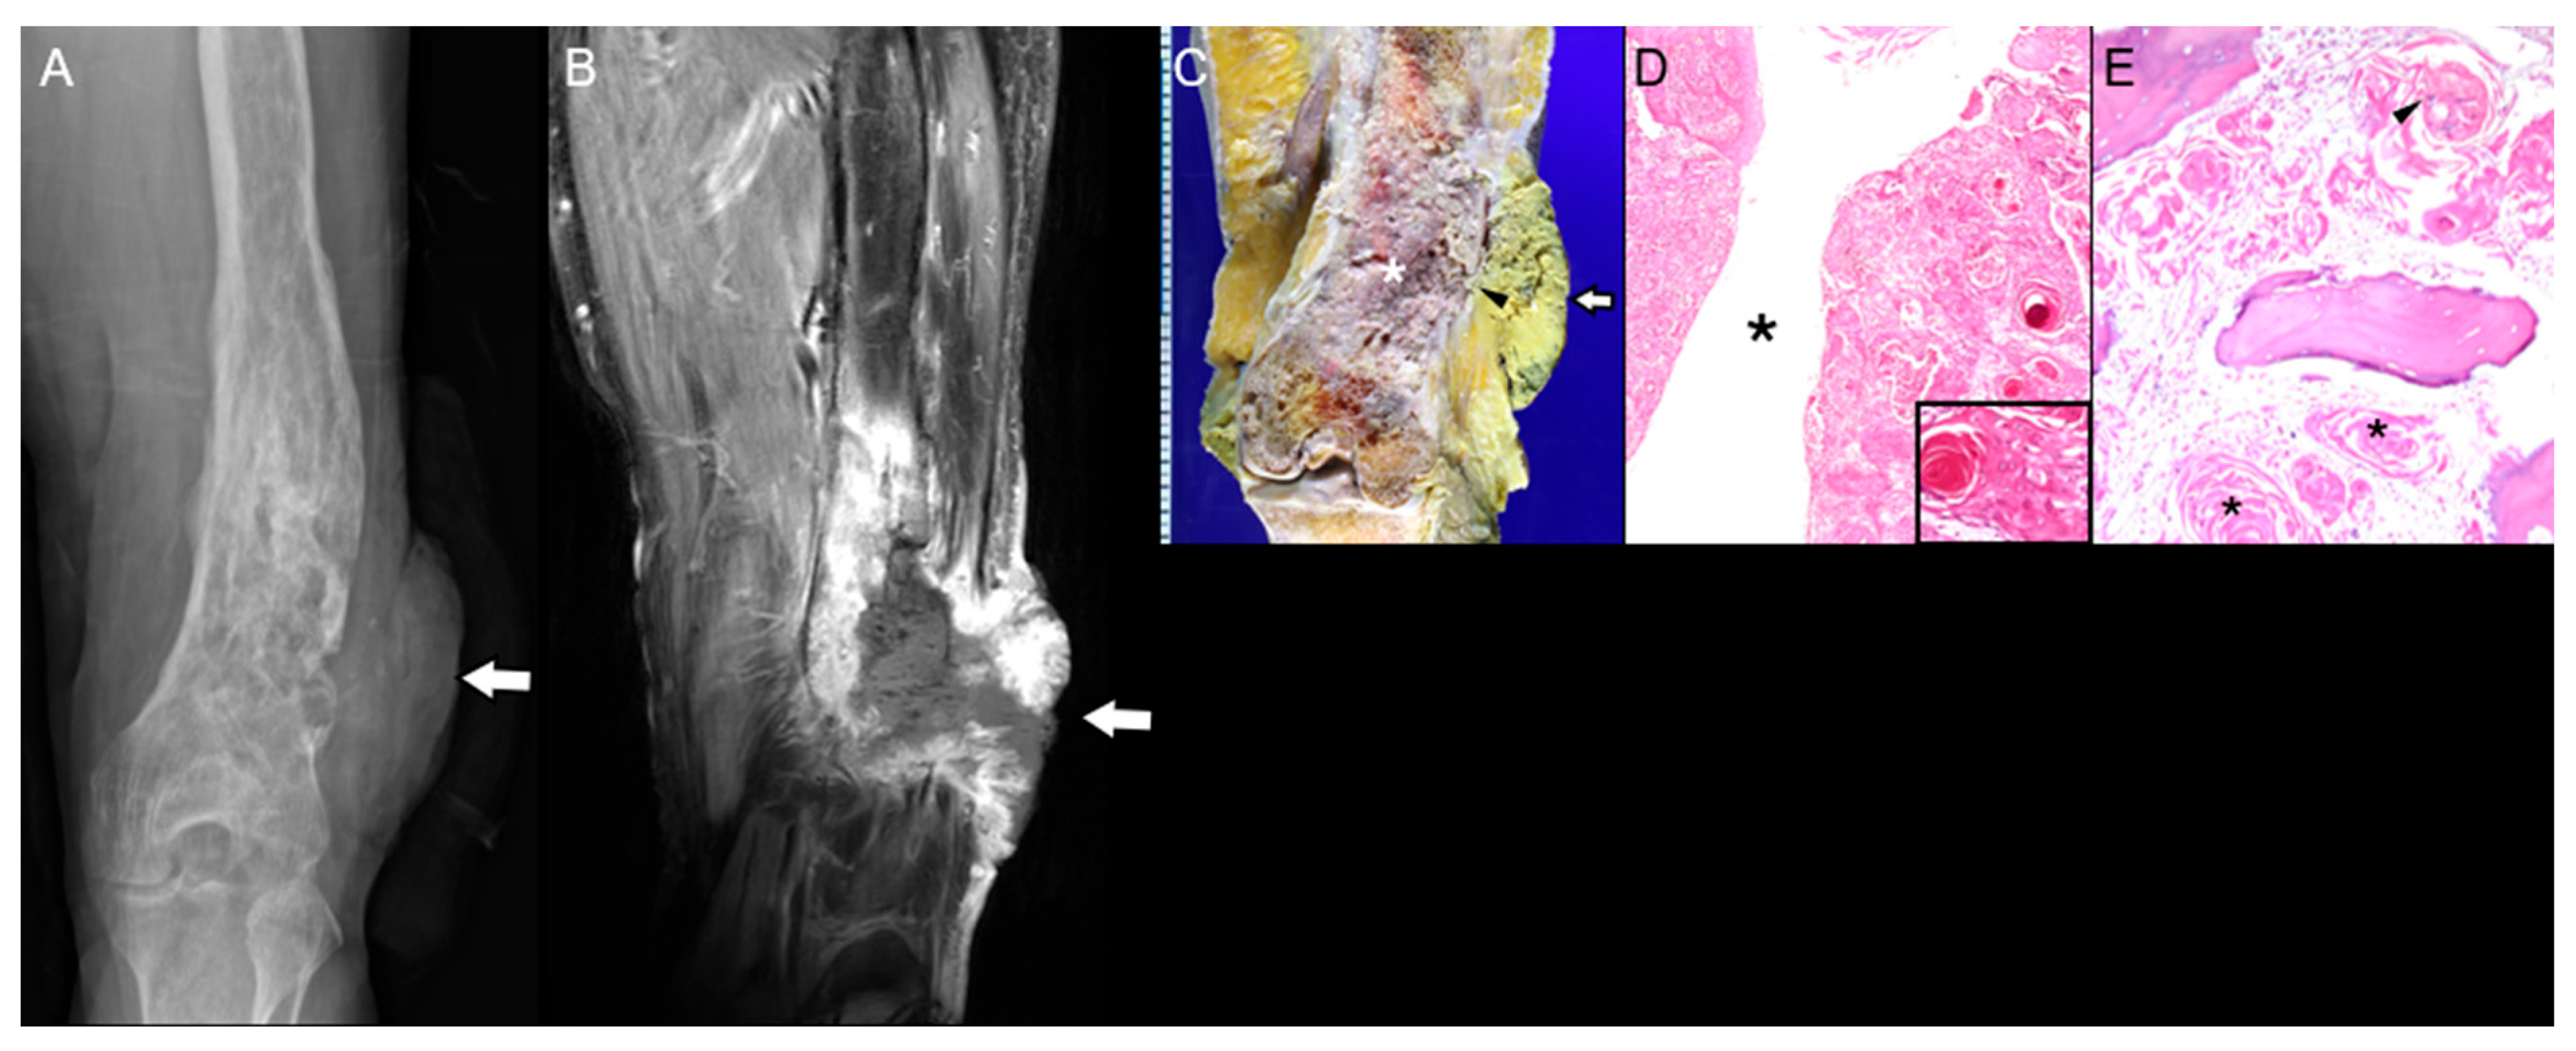

3.1. Chronic Osteomyelitis